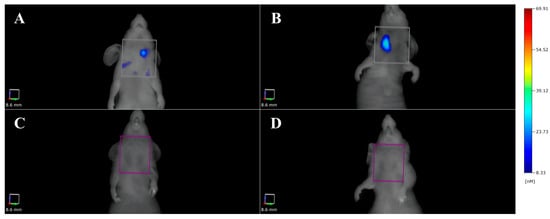

- Liu, Y.; Gunda, V.; Zhu, X.; Xu, X.; Wu, J.; Askhatova, D.; Farokhzad, O.C.; Parangi, S.; Shi, J. Theranostic near-infrared fluorescent nanoplatform for imaging and systemic siRNA delivery to metastatic anaplastic thyroid cancer. Proc. Natl. Acad. Sci. USA 2016, 113, 7750–7755. [Google Scholar] [CrossRef] [PubMed]

| FMT | 8505C-BRAF V600E—Xenograft 8505C-BRAF V600E—Orthotopic | ATC | Therapy effect | [44] | |